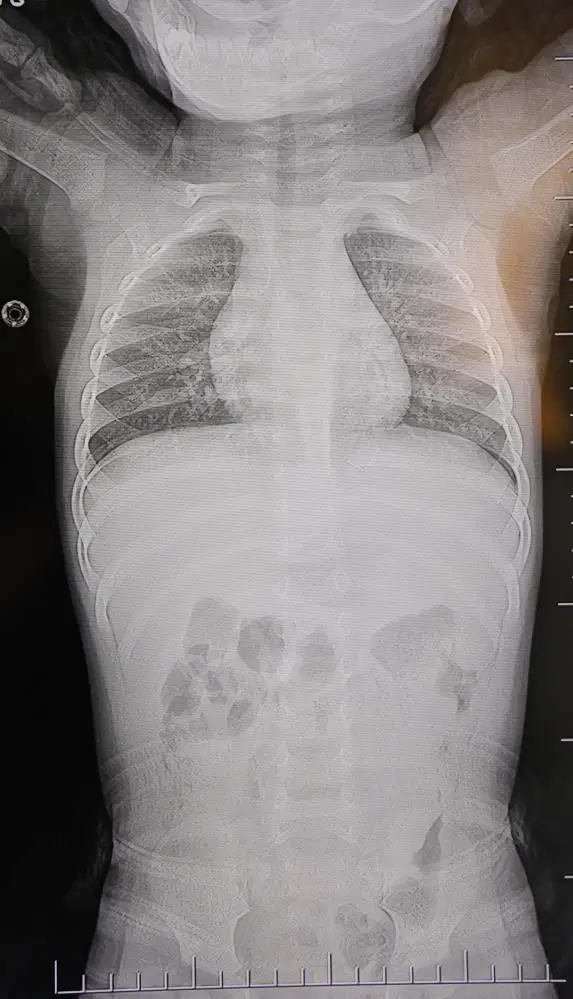

Kahramanmaraş'ta sırt üstü yatmak istemeyen, yatırıldığında ağlama ve huzursuzluğu nedeniyle hastaneye götürülen bir yaşındaki bebeğin sırtından akciğer zarına doğru ilerleyen 2 santimetrelik zımba teli çıktı.

Ailenin başvurduğu hastanede görev yapan Beyin ve Sinir Cerrahisi Uzmanı Prof. Dr. İdris Altun tarafından yapılan tetkiklerde, yabancı cismin cilt altında, omurilik kanalına yakın bir bölgede olduğu ve akciğer zarına doğru ilerlediği belirlendi. Hasta, genel anesteziye alınmadan, lokal anestezi ve sedasyon eşliğinde ameliyata alındı. Yapılan müdahalede yabancı cisim tamamen çıkarıldı. Çıkarılan cismin, ince zımba teline benzer metal bir tel olduğu ve yaklaşık 2 santimetre uzunluğunda bulunduğu tespit edildi. Hasta, aynı gün taburcu edildi.

Konuya ilişkin açıklama yapan Prof. Dr. İdris Altun, "Sırtında yabancı bir cisim olduğu söylenmiş ancak çıkarılamayacağı ve 8 yaşına kadar beklenmesi gerektiği ifade edilmişti. Bize başvurduğunda yaptığımız tetkiklerde, cilt altında, omurilik kanalına çok yakın ve akciğer zarına doğru ilerleyen bir yabancı cisim tespit ettik. Hastamızı tamamen uyutmadan, lokal anestezi ve sedasyon eşliğinde müdahale ederek lezyonu tamamen çıkardık. Çıkardığımız cismin ince zımba teline benzer, yaklaşık 2 santimetre uzunluğunda metal bir tel olduğunu gördük. Bu yabancı cisim alınmasaydı, bölgede enfeksiyon gelişebilirdi. Enfeksiyon sonucu omurilik kanalında ciddi hasarlar oluşabilir, çocuk büyüdükçe cismin hareket etmesine bağlı olarak omurilikte zedelenmeler meydana gelebilirdi. Ayrıca yana doğru ilerleyerek akciğer zarına ve akciğere batma riski vardı. Bu da enfeksiyona ve ilerleyen süreçte tümörle karışabilecek tablolara neden olabilirdi. Şu an hastamız gayet sağlıklı. Gerekli kontrolleri yaptık ve aynı gün taburcu ettik" dedi.